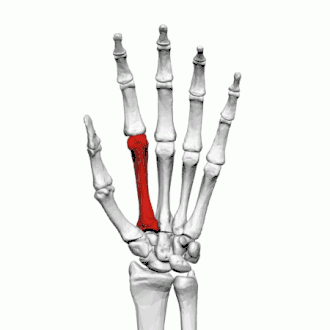

Troisième métacarpien

Description

Le troisième métacarpien est plus court que le deuxième métacarpien.

Base

Sur la face dorsale de sa base se présente sur son côté radial une éminence pyramidale : le processus styloïde du troisième os métacarpien, qui s'étend vers le haut en arrière du capitatum. Dans la partie supérieure se trouve une surface rugueuse pour l'insertion du muscle court extenseur radial du carpe.

La facette articulaire carpienne est concave en arrière, plate en avant et s'articule avec le capitatum.

Du côté radial se trouve une facette lisse et concave pour l'articulation avec le deuxième métacarpien, et du côté ulnaire deux petites facettes ovales pour le quatrième métacarpien.

Corps

La diaphyse donne naissance aux deuxième et troisième muscle interosseux dorsaux de la main.